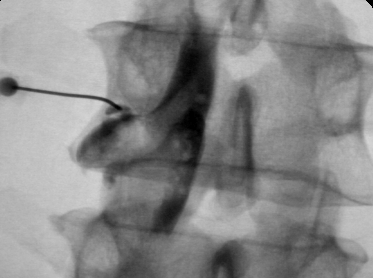

Фораминальная рецидивная грыжа 5 мм. Дискография.

Сдавление корешка L4 в корешковом канале, несмотря на малые размеры грыжи. Эпидурография.